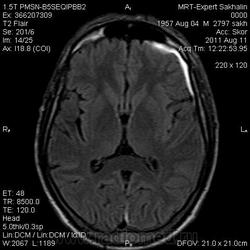

Оболочечная гематома.

Мужчина .Направительный диагноз: чмт (от 29.07.11), гематома головного мозга?

Краткий анамнез заболевания, жалобы: беспокоят головные боли, нарушение речи, онемение правой руки.

субарах левая теменная (или суммация по аксиалам?), линза сбоку... и субдуральное по переферии чтоли?

нет субараха - поторопился